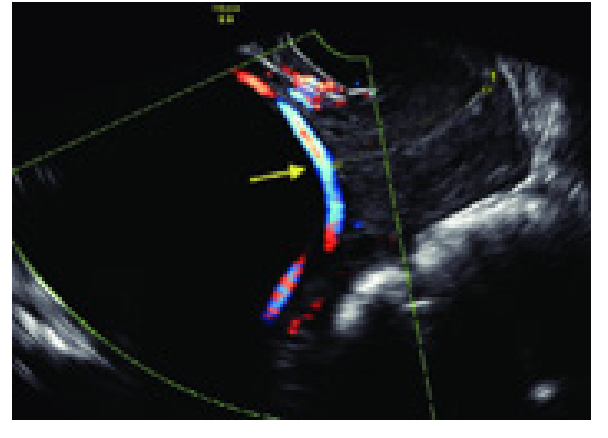

O Espectro do Acretismo Placentário

Em pacientes com Cesárea Anterior + Placenta Prévia, o risco de acretismo (invasão do miométrio pela placenta) é altíssimo.

- Diagnóstico: USG com Doppler ou Ressonância Magnética (principalmente para placenta posterior).